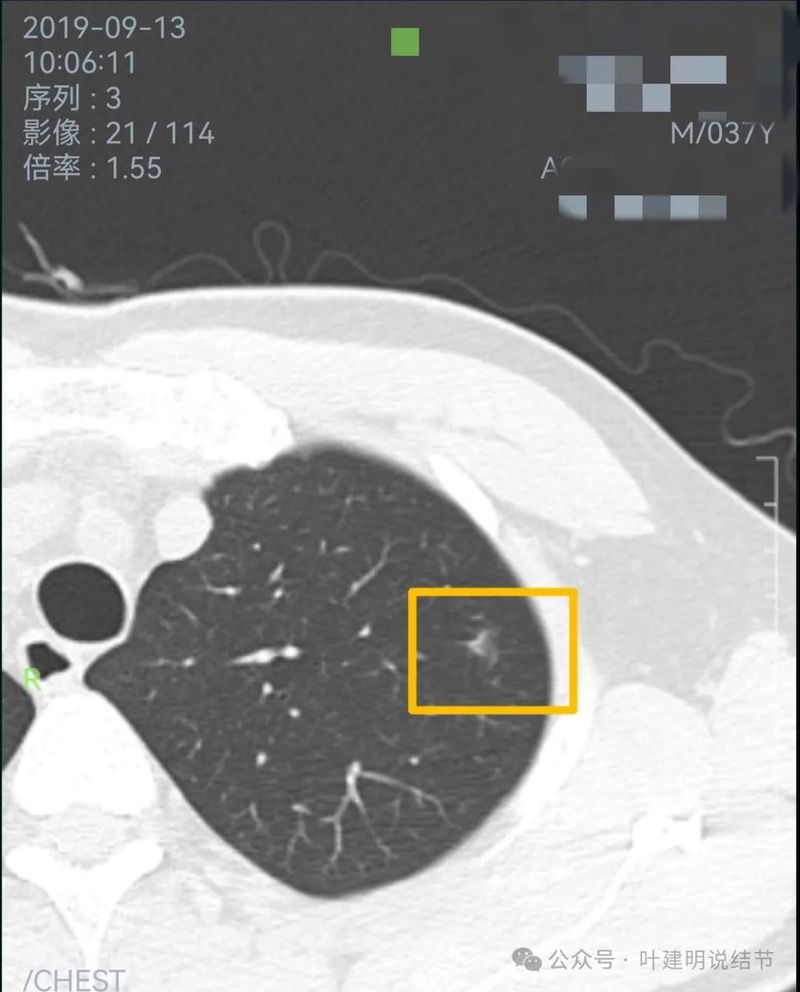

2019年9月左上叶的磨玻璃结节,轮廓稍显模糊,有血管贴边,膨胀性不足。似乎更符合良性点。